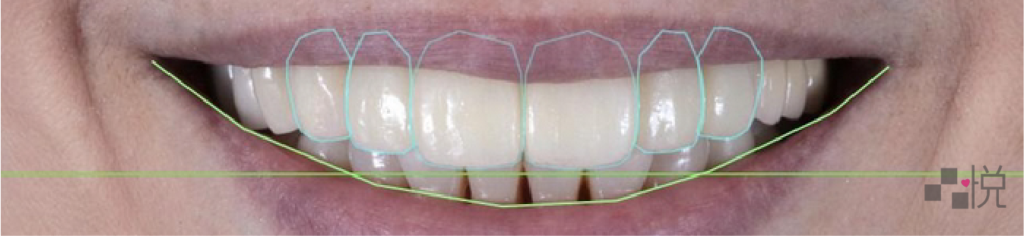

之後依照咬合版的高度製作臨時假牙,試戴兩個月後,確認發音、咀嚼、外觀都沒有問題,便更換為正式假牙完成治療。

整個療程盡可能安排在寒暑假,且使用咬合板或臨時假牙先做觀察,輔以數位微笑曲線設計及數位印模,讓須就診的次數降到最低。

簡單提高咬合,不只改善關節問題,做出了微笑曲線,也讓臉型更漂亮、嘴角的紋路變少。